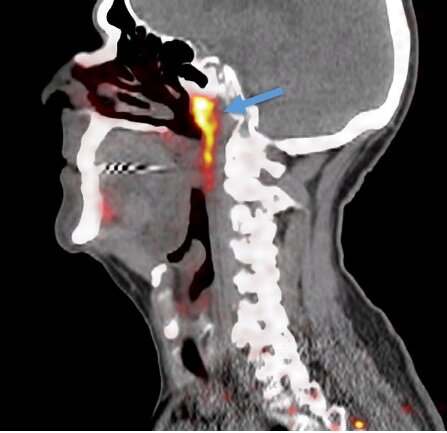

Эта потенциальная четвертая пара находится рядом с местом, где носовая полость встречается с горлом. Исследователи заметили эти незнакомые структуры при просмотре компьютерных томографов 100 пациентов с диагнозом рака простаты или уретры. Затем они исследовали ткани двух трупов и обнаружили, что структуры похожи на слюнные железы, расположенные под языком, о чем они сообщили в журнале «Радиотерапия и Онкология».

Предполагаемая  четвертая пара